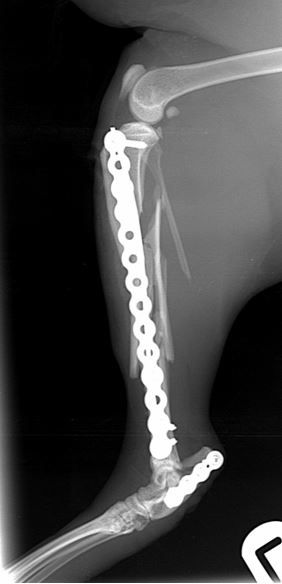

Immediate post-operative radiographs        Immediate post-operative radiographs

Fig. 2 Immediate post-operative radiographs. A 2.4mm PAX plate with an intra-medullary pin has been used to repair the tibial fracture. A 2.0mm PAX plate has been used to repair the comminuted calcaneal fracture